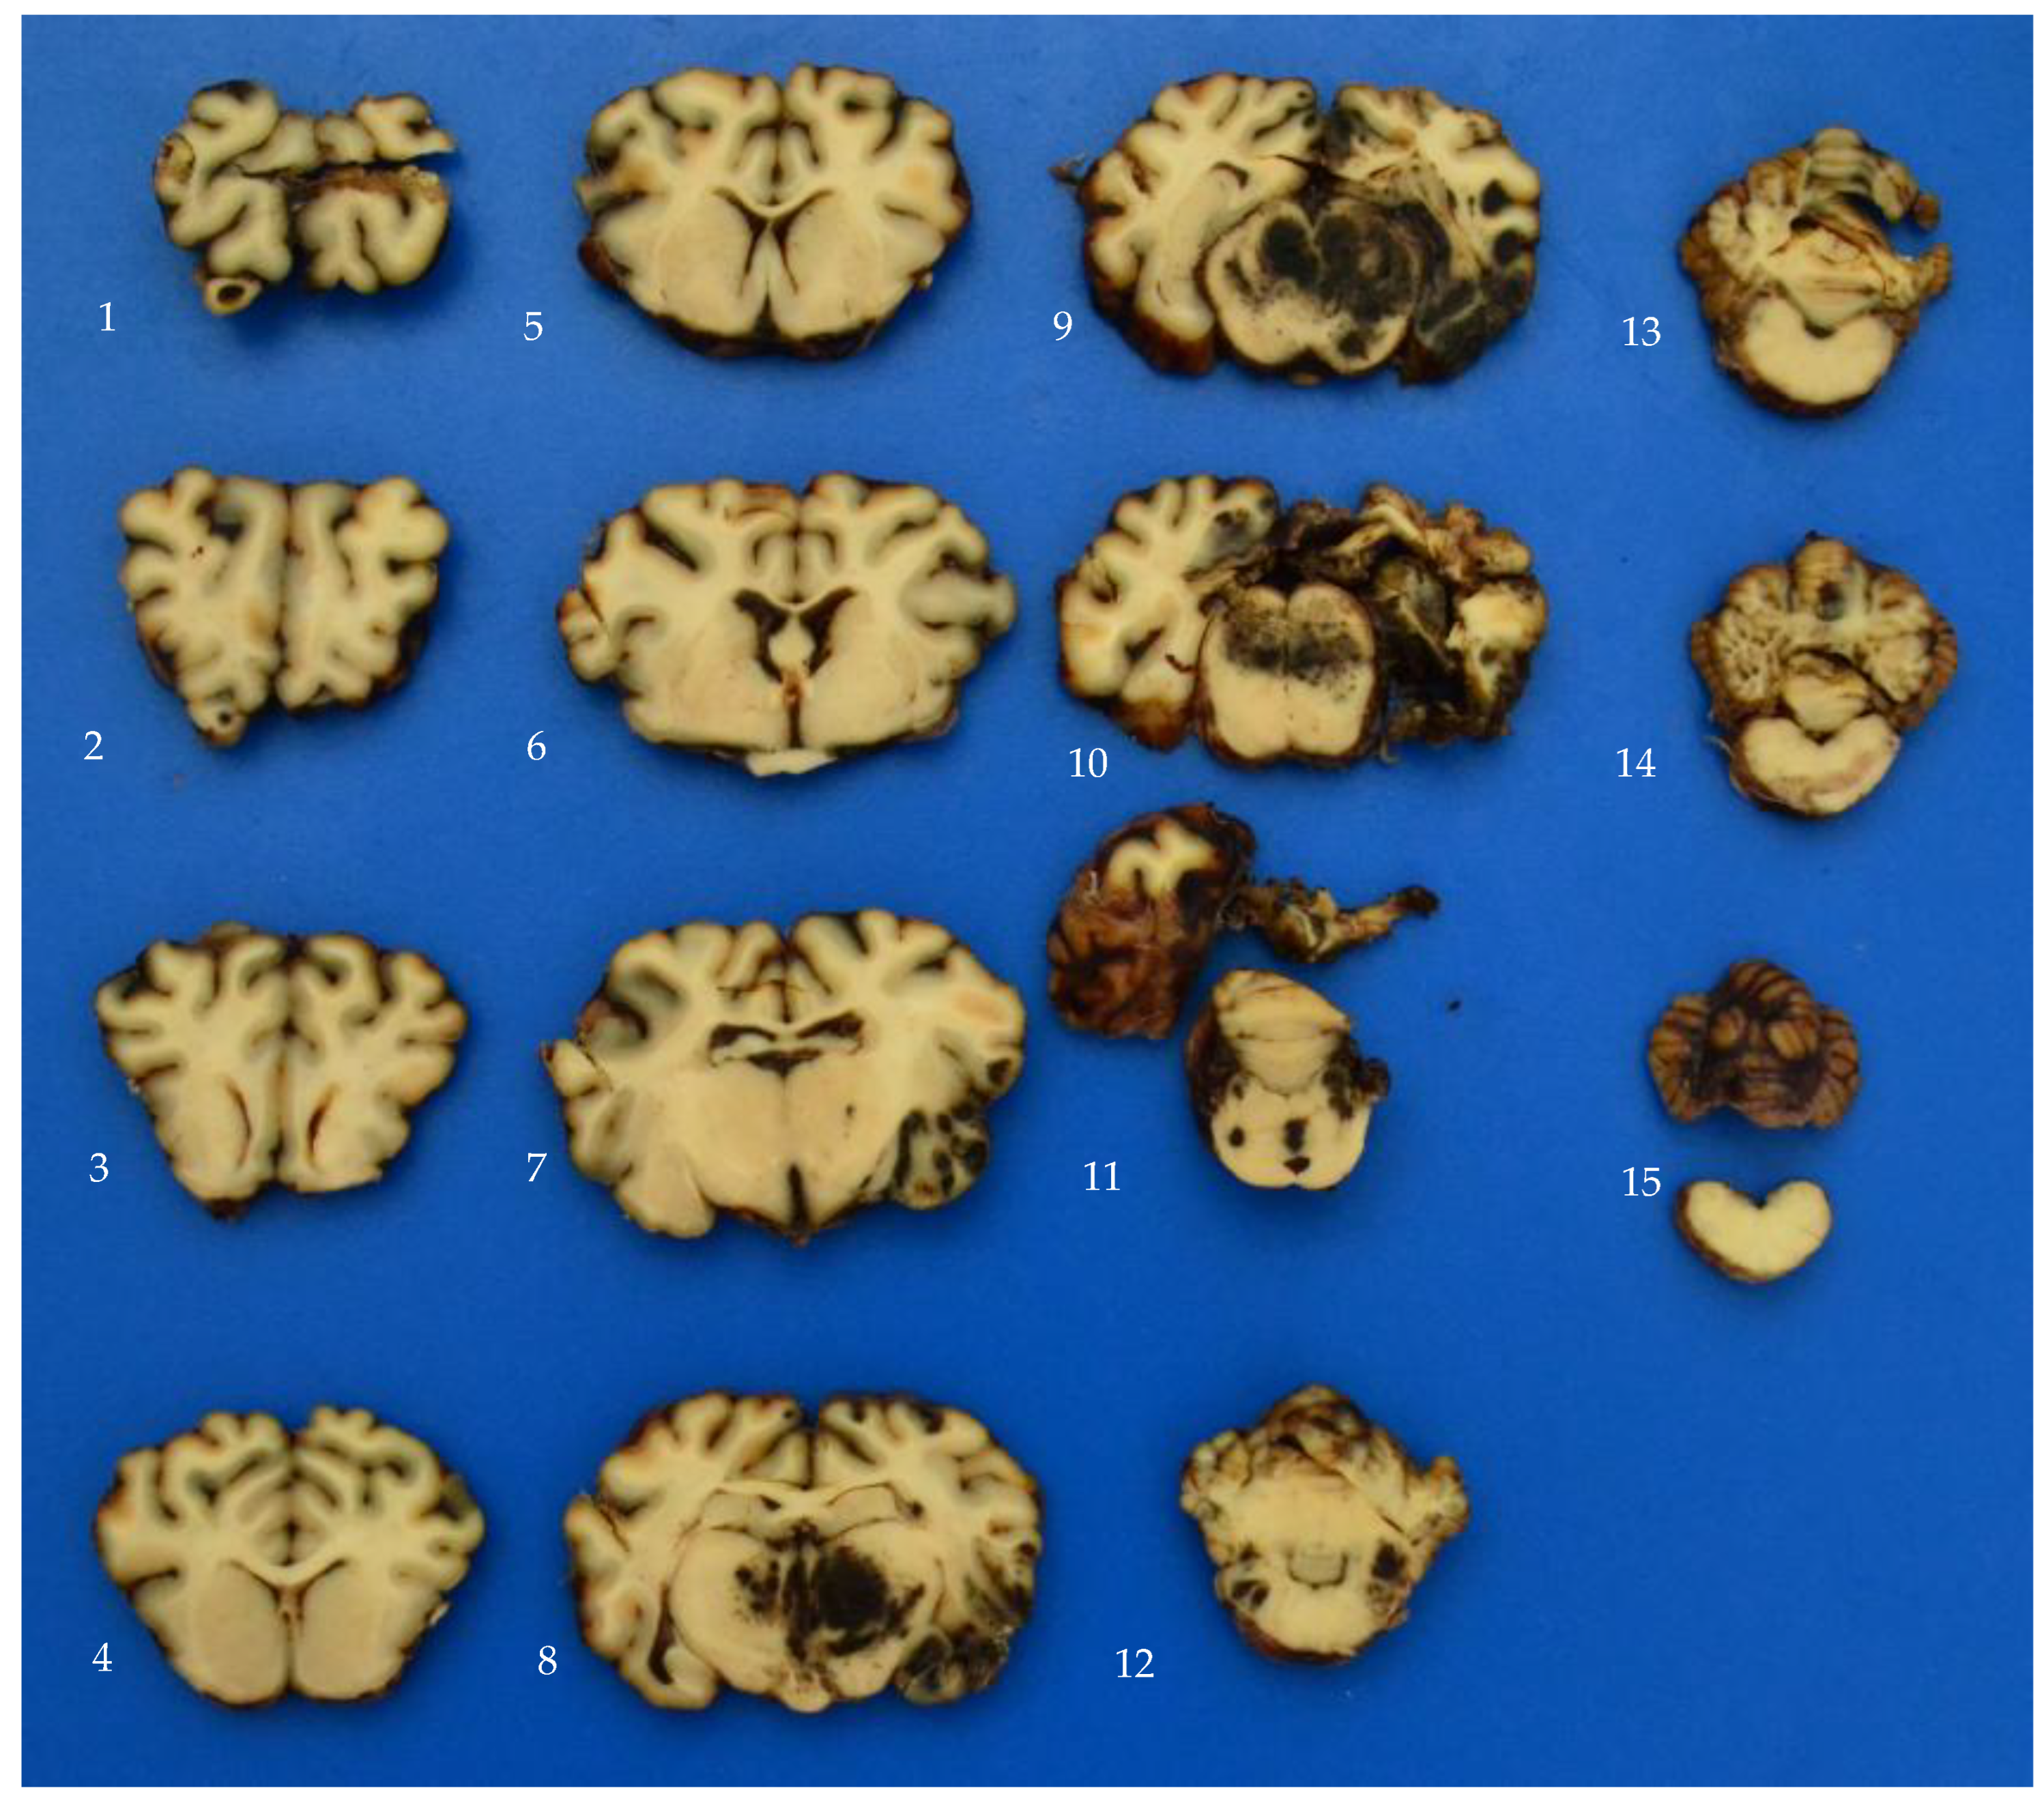

2.3. Gross Fixed Pathology and Histopathology

3.2. MRI, Gross Fixed Pathology and Histopathology